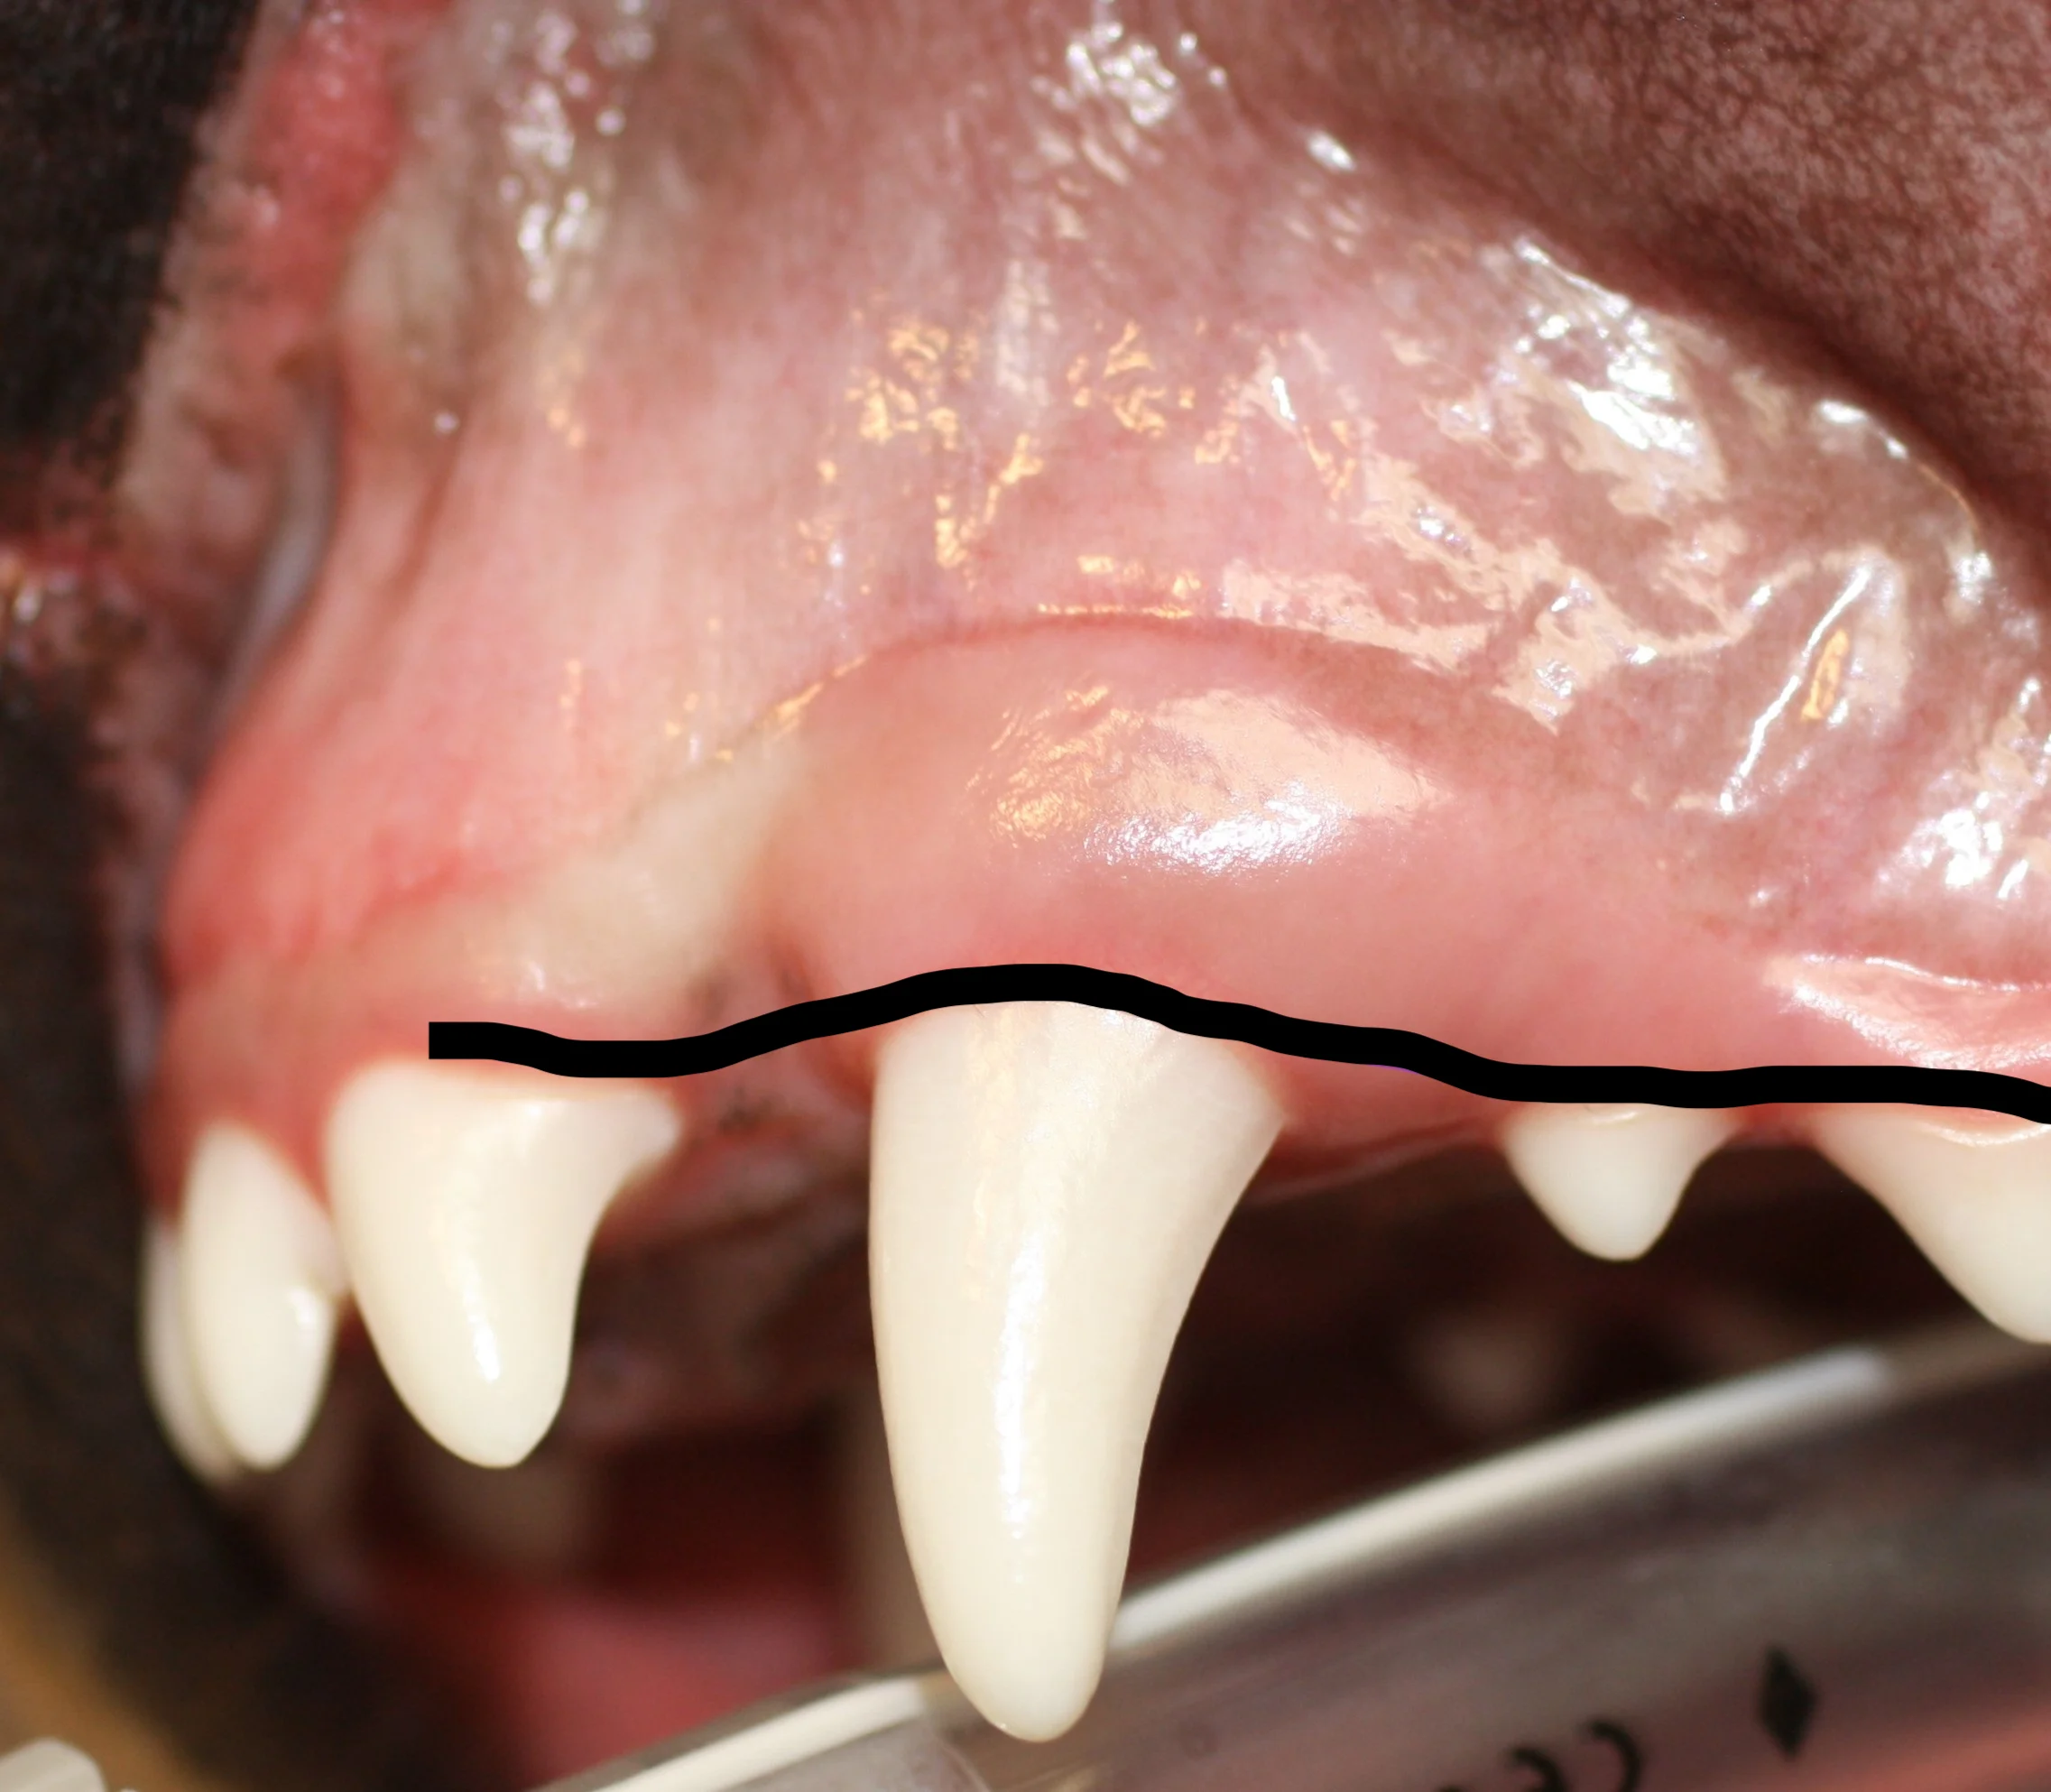

In cats, canine teeth are nearly cylindrical (root is not wider; A), so simple elevation may be sufficient, particularly if the tooth is already mobile due to chronic alveolitis or osteitis in older cats. In these cats, the gingiva may be very thin, making full-thickness mucoperiosteal flap creation challenging. In most dogs, however, the diameter and width of the root is broader than the widest part of the crown at the neck of the tooth, with a larger dimension from front to back (mesial to distal) than side to side (buccal to palatal; B). A full-thickness pedicle mucogingival flap with alveolar bone removal is recommended for both species but is more critical in dogs.

A